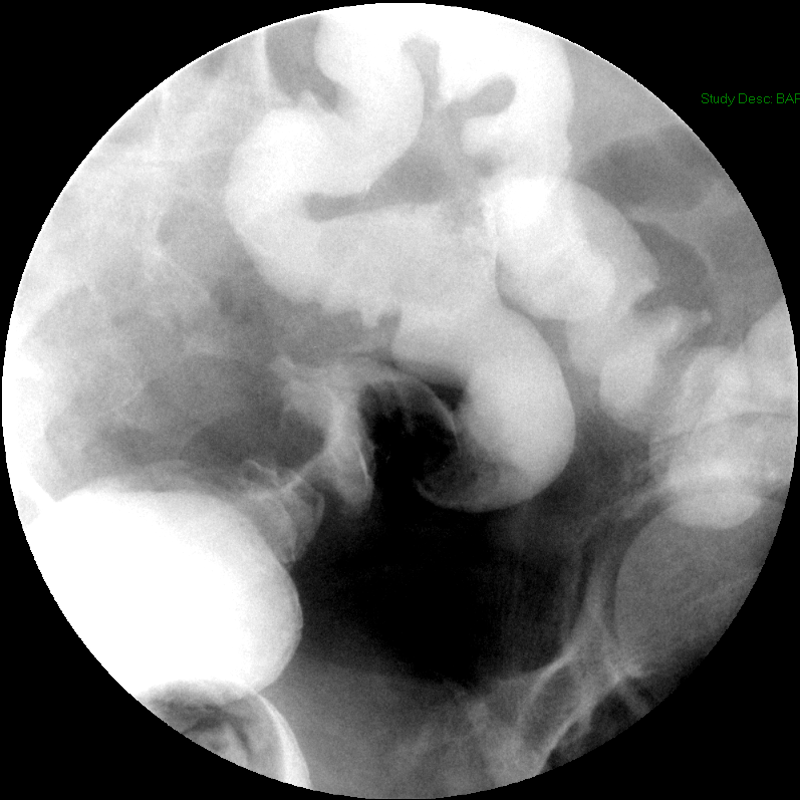

- The gynecologist will begin injecting contrast material into the uterus. Obtain images periodically throughout the procedure (usually at the direction of the gynecologist). The images should include the uterine cavity filled with contrast material, bilateral fallopian tubes filled with contrast material, and spillage and dispersion of contrast material into the peritoneal cavity (image 1) (image 2) (image 3) (image 4) (image 5).